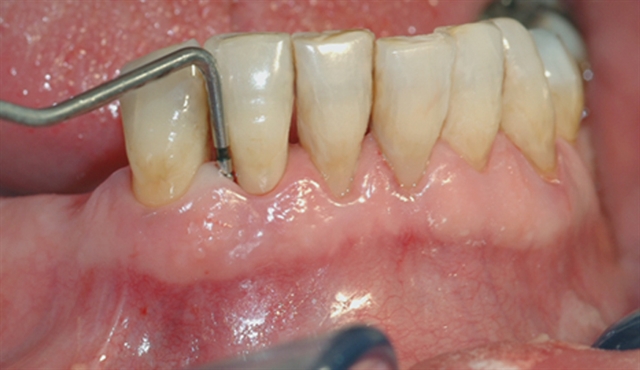

Bildet viser et nærbilde av tennene i underkjeven med tannsten og misfarging.

Bildet viser forholdene i underkjeven etter at tannsten og misfarging er fjernet